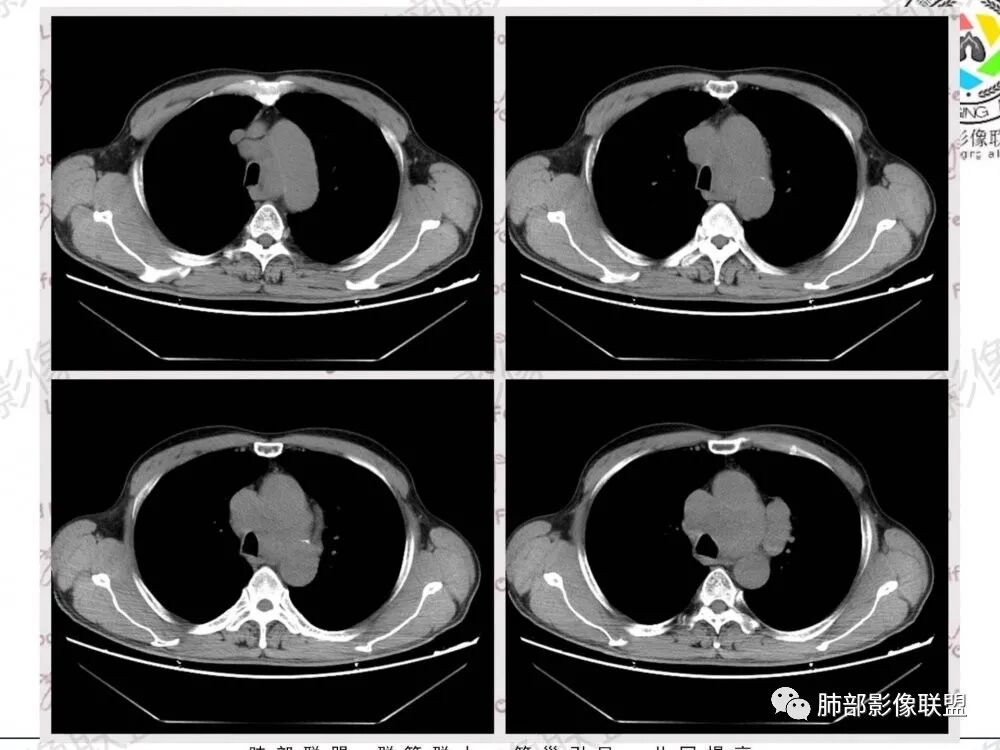

1.左肺门及纵隔见异常增大淋巴结,部分融合,不均匀轻度强化,未见明显坏死。

肿大淋巴结与纵隔血管等结构“无缝”贴合。

2.纵隔增宽但依旧居中。

2、小细胞癌恶性程度高,发展迅速,转移发生早;常有纵隔淋巴结的明显增大融合(发生率达96.5%),呈“冰冻纵隔”,淋巴转移常为逐站的连续性转移;亦有血行转移,脑、肾上腺、肝、胰、骨髓等;转移灶常比原发灶大得多,即“娘小崽大”特点;